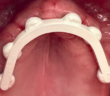

LE POINT DE CONTACT EN PROTHÈSE UN POINT CLÉ POUR L’ESTHÉTIQUE ET LA FONCTION

POINT DE CONTACT INTERPROXIMAL EN ZONE ESTHÉTIQUE POINT DE CONTACT INTERPROXIMAL ET ESTHÉTIQUE GINGIVALE EN SECTEUR ANTÉRIEUR L’esthétique gingivale en…